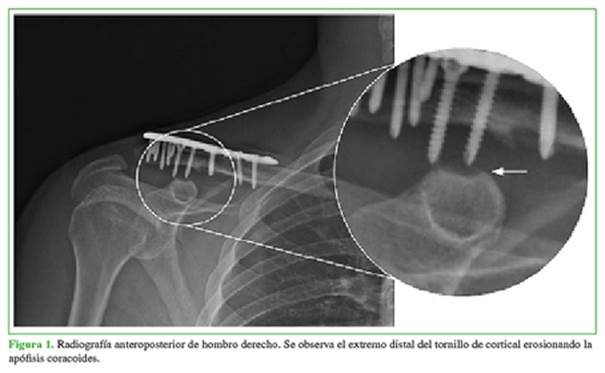

A los seis meses de la cirugía, comenzó con un dolor limitante y creciente en el hombro derecho, por lo que decidió consultar, en esa oportunidad, en nuestra institución. En el examen físico, se detectó hipersensibilidad a nivel de la apófisis coracoides con impotencia funcional del hombro debido al dolor severo, 9/10 en la escala analógica visual. Se tomaron radiografías de clavícula y hombro, de frente, de perfil y proyección de Zanca, en las que se observó la erosión de la apófisis coracoides causada por el contacto del extremo distal del tornillo de cortical utilizado en la placa bloqueada de compresión (Figura 1). Se decidió realizar una tomografía computarizada tridimensional para evaluar correctamente la extensión de la lesión (Figura 2).